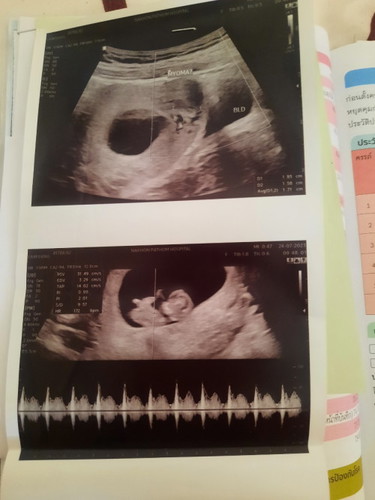

ภาพแรกคะมีก้อนเนื้องอก

เราเป็นเนื้องอก ตรวจสุขภาพประจำปีทุกปี และตรวจมะเร็งปากมดลูก เลยรู้ หมอบอก เวลามีประจำเดือนเลือดจะออกเยอะ หรือ ทำให้ท้องยาก แต่เราปล่อย 3 เดือน ติดค่ะ น้องมา หมายถึงติดค่อนข้างง่าย หมองง มาได้ยังไง😅 แล้วไอ้ก้อนนี้ก็มีปัญหา ช่วง 8-10w ปวดท้องเหมือน จะไม่รอด ทรมานสุดๆ ต้องฉีดยากันแท้งทุกสัปดาห์ แต่ตอนนี้หายปวดแล้วค่ะ แต่ก้อนนี้อาจจะ ทำให้คลอดก่อนกำหนด หรือ ทำให้ลูกตัวเล็ก เพราะไอ้ก้อนนี้ มาแย่งอาหารจากเบบี๋ไป เราต้องกินบำรุงแต่ของที่มีประโยชน์เยอะๆค่ะ เพราะว่าเรามีไอ้ก้อน กับ ลูก

อ่านเพิ่มเติมแม่บ้านนี้ท้องได้12w2วันหมอซาวครั้งแรกบอกในมดลูกใม่มีอะไรพอไปซาวรอบที่บอกมีเนื้องอกอาจจะขวางทางคลอดคิดกลัวไปหมดเลยคะอายุก็เยอะแล้วท้องนี้เป็นความหวังของพ่อกะแม่มาก